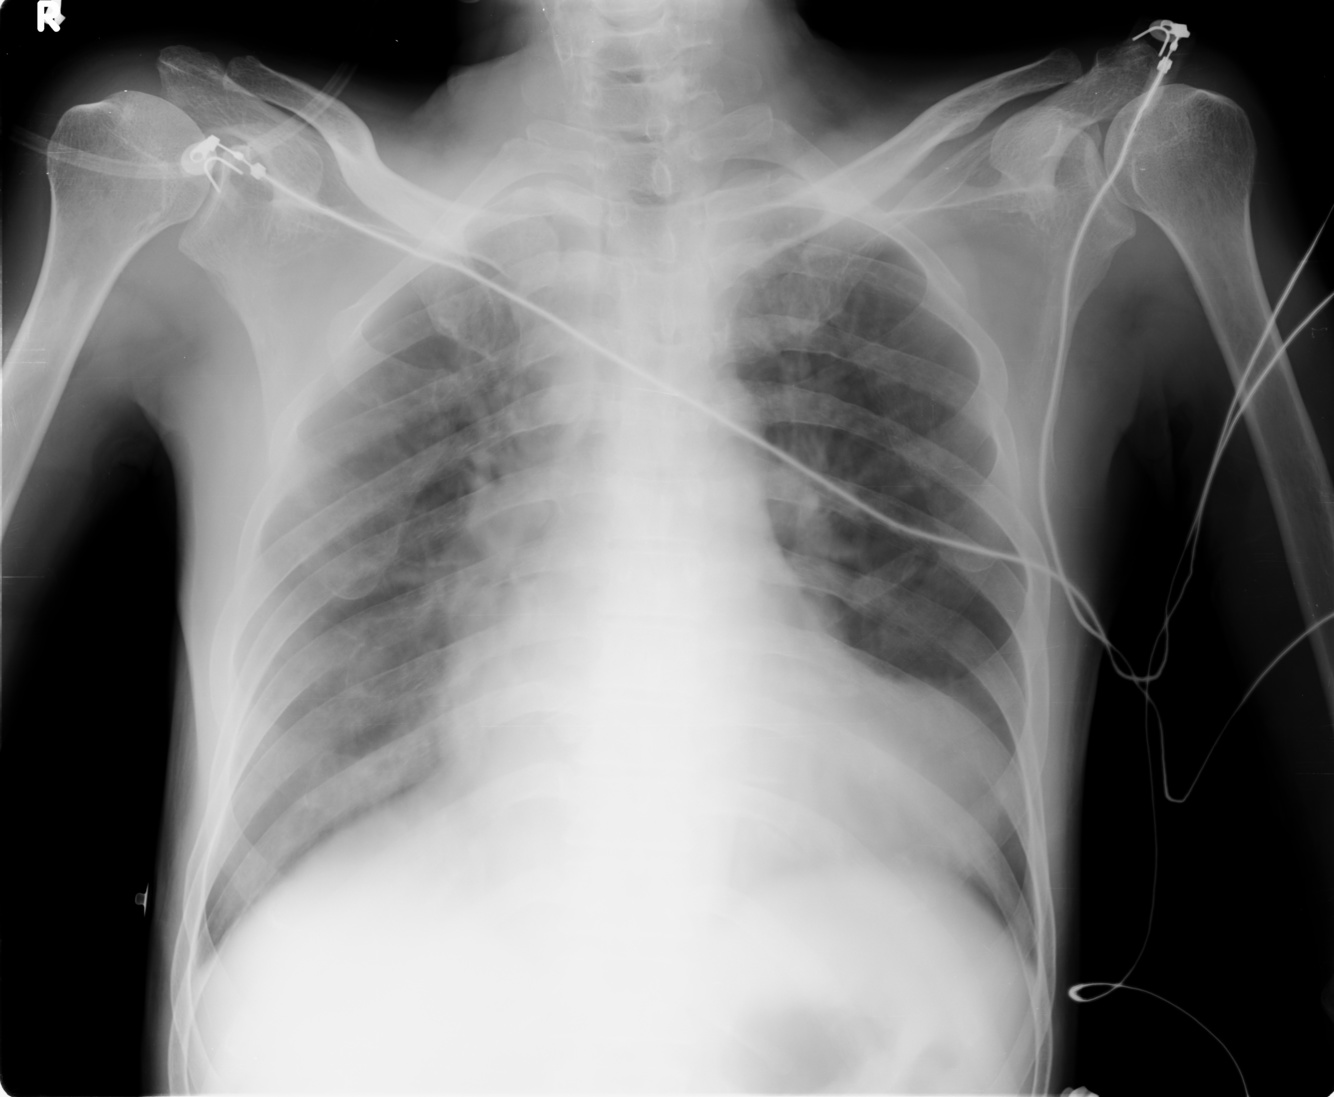

Heart Failure

(- prosthetic valves)

LVA

Pulmonary edema

+- pleural effusions

+- heart failure